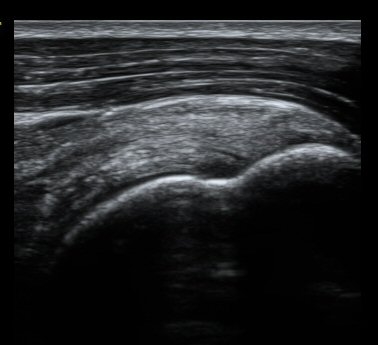

ȸÀü±Ù°³°£°Ý ³»Ãø Ⱦ´Ü¸é°Ë»ç¿¡¼­ °üÂûÇÑ °ß°©ÇÏ±Ù°Ç »óºÎ Á¾´Ü¸é°Ë»ç¿¡¼­ ¹Ì¼¼ÇÑ °£±ØÀÌ

°üÂûµÊ(±×¸² 3, 4). °ß°©ÇÏ±Ù°Ç È¾´Ü¸é°Ë»ç¿¡¼­µµ °ß°©Çϱٰdz» °£±ØÀÌ °üÂûµÊ(±×¸² 5).